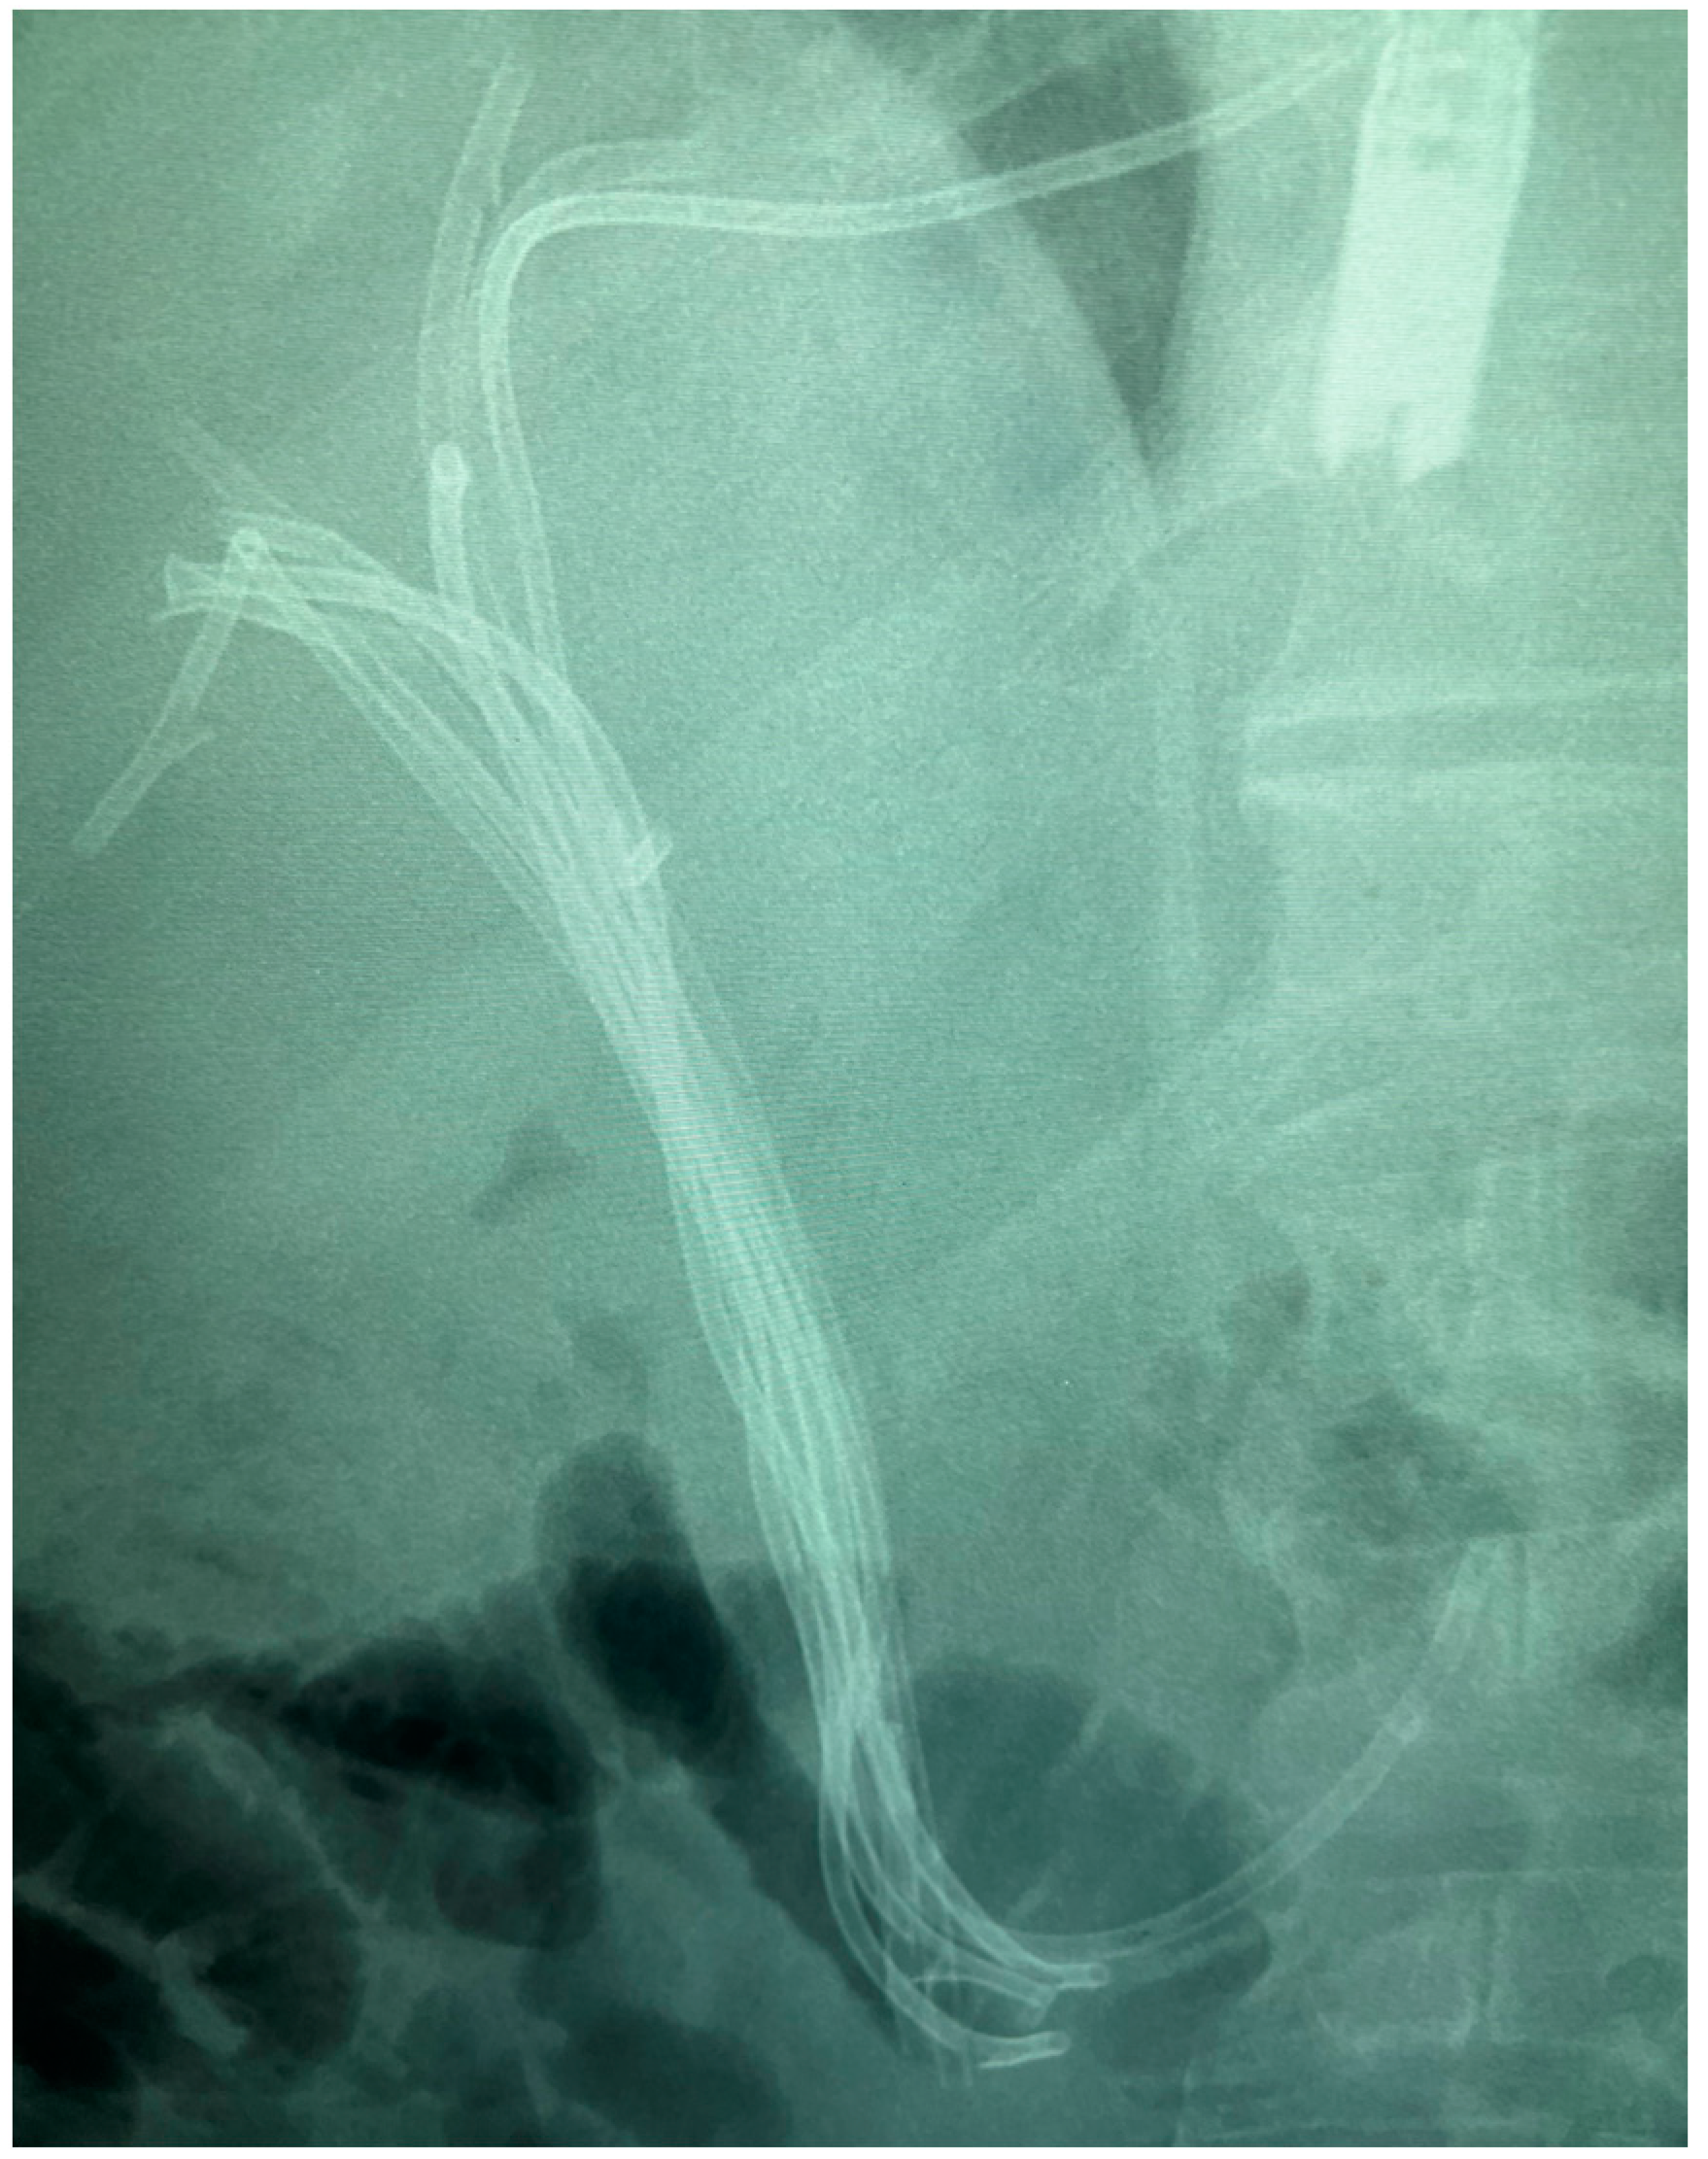

7.1.2. Endoscopic Nasobiliary Drainage (ENDB)

7.1.3. EUS-Guided Biliary Drainage (EUS-BD)

- Kawashima, H.; Itoh, A.; Ohno, E.; Itoh, Y.; Ebata, T.; Nagino, M.; Goto, H.; Hirooka, Y. Preoperative endoscopic nasobiliary drainage in 164 consecutive patients with suspected perihilar cholangiocarcinoma: A retrospective study of efficacy and risk factors related to complications. Ann. Surg. 2013, 257, 121–127. [Google Scholar] [CrossRef]